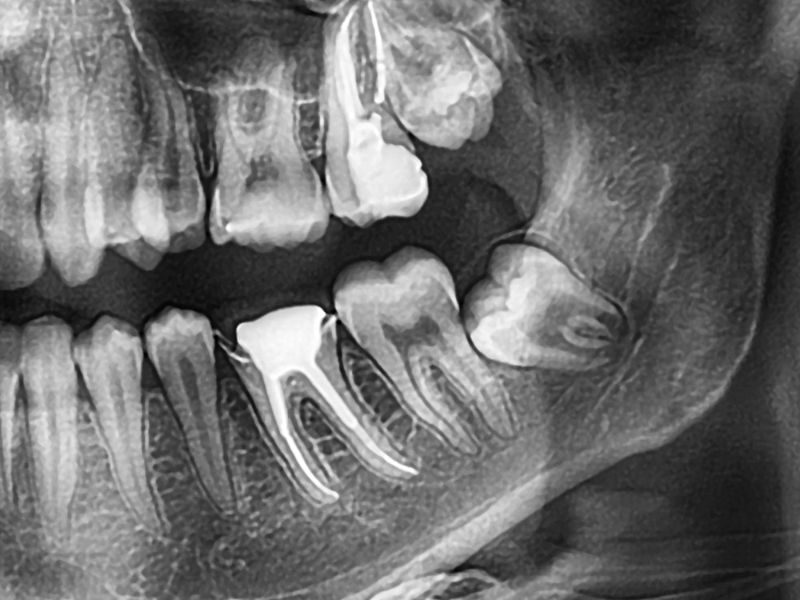

Wisdom teeth extraction in Brambleton is a routine procedure that removes these problem teeth before they damage your smile. We carefully map out your teeth and jaw with high-tech digital X-rays and imaging. This helps us make a plan for a very specific and gentle wisdom teeth removal in Brambleton that is perfect for you.

Some people's wisdom teeth don't cause problems, but when they do, it's best to do something about them right away. Impacted or misaligned molars can press on nearby teeth, create gum pockets that trap bacteria, or even cause cysts to form. Removing them protects your bite and keeps your mouth healthy.